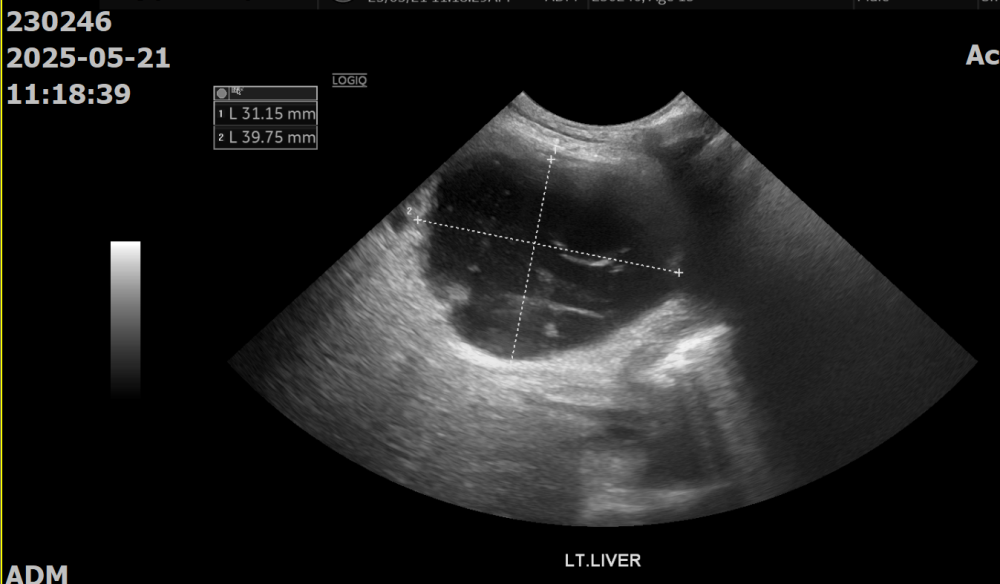

복부초음파상에서도 마찬가지로 불균질한 고에코성의 췌장 실질, 주변 복막염이 관찰되었습니다. 추가로, 간에 Cystic한 mass가 관찰되었습니다.

간 병변에 대해 초음파 유도 세침흡인을 시행한 결과, 다수의 호중구 침윤과 퇴행성 변화, 그리고 괴사성 debris가 관찰되어 화농성 염증이 강하게 의심되었습니다.